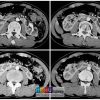

V. Chẩn đoán UIV / CT

– Hai thận xoay trục, cực dưới hướng vào trong phía cột sống.

– Đài bể thận bình thường hướng lên trên ra ngoài => hướng xuống dưới.

– Phần nối hai cực dưới là nhu mô hoặc dải xơ vắt ngang phía trước cột sống.

=> Case lâm sàng 3:

=> Case lâm sàng 4: